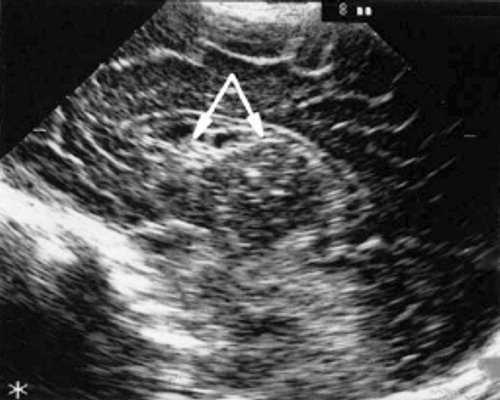

У детей этой группы при первом эхоэнцефалографическом исследовании были выявлены субэпендимально расположенные кистозные структуры на уровне таламо-каудальной вырезки (ТКВ) и (или) кпереди от нее диаметром от 0,3 до 1,1 см. У части новорожденных субэпендимальные кисты были представлены единой полостью с однородным или неоднородным содержимым, у других детей эти структуры напоминали соты, т. е. состояли из множества жидкостных включений, окруженных эхопозитивным ободком (рис. 3). Эти структурные особенности субэпендимальных кист, по-видимому, обусловлены разными стадиями резорбции. У 10 детей субэпендимальные кисты располагались в симметричных участках обоих полушарий, у 2 новорожденных - только в левом полушарии. У 3 детей, помимо субэпендимальных кист, расположенных в таламо-каудальной вырезке и (или) кпереди от нее, дополнительно выявлены субэпендимальные щелевидные кистозные структуры на уровне средних или передних отделов лобных рогов (см. рис. 3).

Рис. 3. Эхоэнцефалограмма ребенка Б. со смешанной герпес-цитомегаловирусной инфекцией, 5-е сут. жизни.

а) Правое полушарие. Стрелками обозначены субэпендимальные кисты, имеющие вид сот, расположенные в таламокаудальной вырезке и кпереди от нее.

б) Левое полушарие. Стрелками обозначены субэпендимальные кисты, имеющие вид сот, расположенные в таламокаудальной вырезке и кпереди от нее.